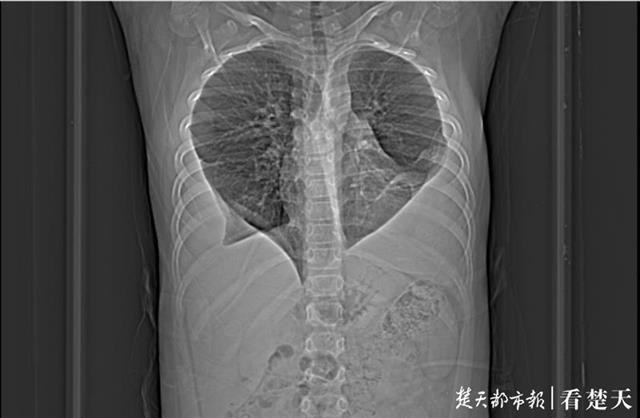

拍片发现,嘉嘉的肺部形态很是奇怪——像桃心的两半一样,中间被气管连接在一起,原本肺部下端则被不明物体所覆盖 。进一步检查发现,嘉嘉确实为肺吸虫感染 。

武汉儿童医院心胸外科主任皮名安介绍,正是肺吸虫感染导致孩子双侧肺都有严重的积液,积液在肺中不断沉积,积液中的蛋白质等物质沉积、钙化形成类似“纤维板”,附着于孩子肺部下端,形成了类似桃心的形状 。